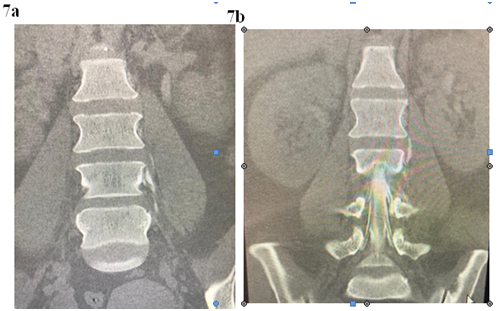

L 1/2 nerve root sleeve demonstrates bilateral small Tarlov’s cysts, the cyst on the left measures up to 4mm in diameter; the right measures up to 2.5mm in diameter; see Figures 7a & 7b.

Figure 7a & 7b Myelogram: Extravasation of contrast into the paravertebral soft tissue around the left lumbar 2/3 Tarlov cyst suggesting a CSF leak at this level.

In the dorsal and lumbar spine several other levels of nerve root Tarlov cysts are identified: none of these described Tarlov cysts show any extravasation into the surrounding soft tissues. 20ml of fresh blood was injected into the epidural space immediately after instillation of contrast into the CSF space. Initially the patient was pain free but required a second patch 1 week later due to return of symptoms.